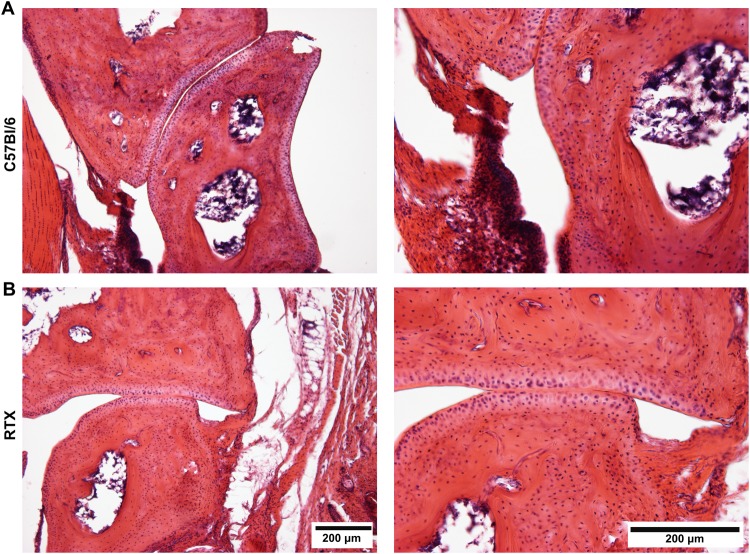

Retained integrity of the articular cartilage

Examination of the histological slides made from the ankle joints obtained on day 21 demonstrated mild synovial proliferation in the tibiotarsal joints of both arthritic groups, but the articular cartilage remained intact (Fig. 5A,B).

Figure 5.

Representative histological slides of the tibiotarsal joints excised at the end of the experiment (day 21) stained with hematoxylin-eosin of (A) arthritic control, and (B) RTX-pretreated mice (100x and 200x magnification).

Histopathological examination of the tibiotarsal joint did not show any major bone and cartilage alterations neither in response to arthritis nor RTX desensitization in our model. These data clearly suggest that micro-CT is more sensitive and sophisticated technique to evaluate arthritis-related microarchitectural bone changes.